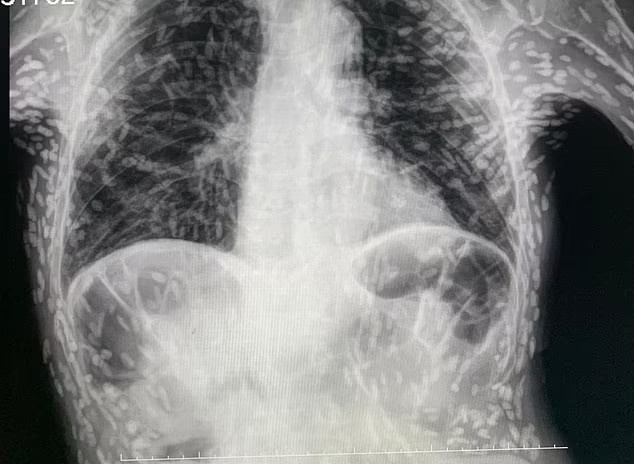

Phim chụp dạ dày cho thấy bệnh nhân bị ho kéo dài do hàng trăm ấu trùng sán dây bị vôi hóa trong người.